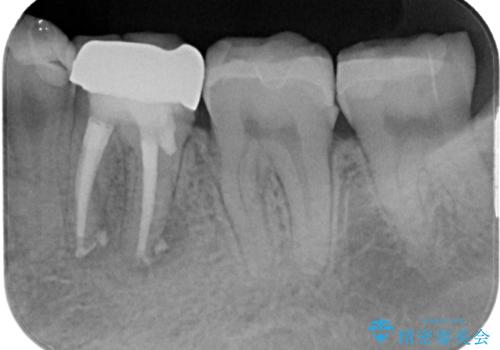

病変が消退しているかどうか、半年、1年とレントゲン写真で経過観察を行う必要があります。

4ヶ月後のレントゲンでは、病変の消退が認められました。